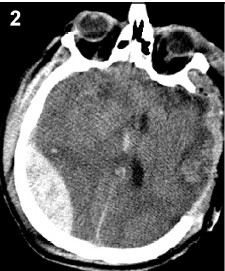

2.2 Postoperative intracranial hemorrhagePostoperative intracranial hemorrhage is a frequent complications secondary to neurosurgical operation (Figure 2),and its incidence is among 1.1% and 6.9%[10]. However,it seems that postoperative intracranial hemorrhage is more frequent in head trauma patients, especially for those who underwent DC. Bullock et al. reported their study about neurosurgical procedures in head trauma patients,and the postoperative intracranial hemorrhage occurred in 6.9% of the total patients[11]. In our study,this complication occurred in 8 cases of total 108 patients who underwent DC for severe TBI (the incidence was 7.4%)[2],and comparing to other neurosurgical operations,the haematomas contralateral to the operative side were more frequent. Besides,intracranial haematoma contralateral to the decompressive side should be mentioned. We have reported fifteen cases complicated with contralateral intracranial haematoma after large DC among patients with severe head trauma[12]. Decompressive surgery releases a tamponade effect of the initial hemorrhage on the contralateral source,which may contribute to the formation of contralateral intracranial haemotoma[12]. In further,the existence of contralateral abnormal signs in the CT scan before the DC,especially cranial fracture and haemotama,would increase the risk of occurrence of postoperative intracranial re-hemorrhage. So these risk factors should be noticed for any patient who is about to undergo DC. Besides,coagulopathy following TBI has a high incidence ranging from 10% to 87.5%,especially among the patients with severe TBI[13]. And a coagulopathy may be responsible for the postoperative intracranial hemorrhage as well.

| Figure 2 The extradural haemotoma contralateral to the decompressive hemisphere can be seen from the CT, and this haemotoma has mass effects and causes a dramatic midline shift |